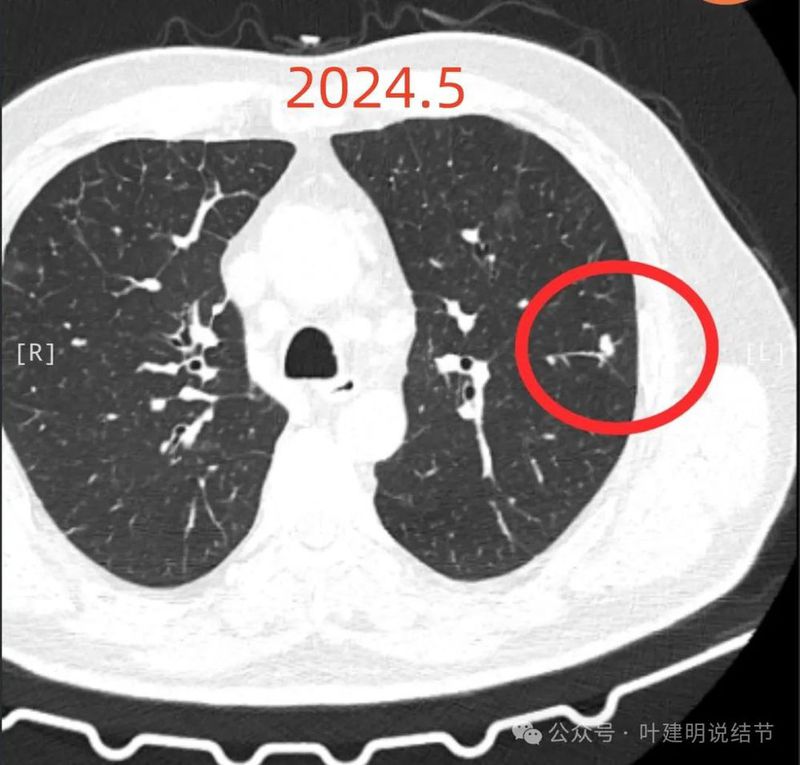

2024年9月再增大进展,见血管进入明显,靠血管这侧的边缘较为毛糙。

局部放大病灶表面不平,血管进入,进入的血管有异常增粗,没有见到明显卫星病灶。